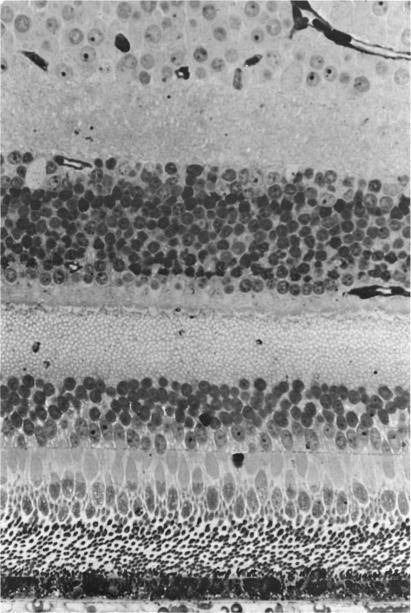

Three major pathologic processes caused by light in the primate retina: a search for mechanisms.

Trans Am Ophthalmol Soc. 1982;80:517-79.